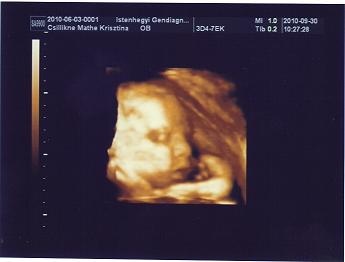

Kriszta, nagyon édi a csajszi, szupi kép! Örülök, hogy minden rendben volt. Minden rendben lesz ezután is!